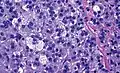

Histopathology

The microscopic histopathology analysis of the tissue samples obtained from the adrenal cortex of individuals presenting with adenoma-associated symptoms such as primary aldestronism (PA) indicates that adenoma cells are relatively larger with different cytoplasm, and increased variation in nuclear size. This indication is based on comparison between the healthy (normal) and affected (adenoma-associated) adrenal cortex tissue samples.

Adrenocortical adenoma with focal high grade nuclear atypia

Adrenocortical adenoma with focal high grade nuclear atypia -

Adrenocortical adenoma with focal necrosis

Adrenocortical adenoma with focal necrosis -

Adrenocortical adenomas are most commonly distinguished from adrenocortical carcinomas (their malignant counterparts) by the Weiss system,[13] as follows:[14]

| Characteristic[14] | Score |

|---|---|

| High nuclear grade (enlarged, oval to lobated, with coarsely granular to hyperchromatic chromatin and easily discernible, prominent nucleoli)[15] | 1 |

| More mitoses than 5/50 high power fields | 1 |

| Atypical mitoses | 1 |

| Eosinophilic cytoplasm in >75% of tumor cells | 1 |

| Diffuse architecture of >33% of tumor | 1 |

| Necrosis | 1 |

| Venous invasion | 1 |

| Sinusoidal invasion (no smooth muscle in wall) | 1 |

| Capsular invasion | 1 |

Total score indicates:[14]

- 0-2: Adrenocortical adenoma

- 3: Undetermined

- 4-9: Adrenocortical carcinoma